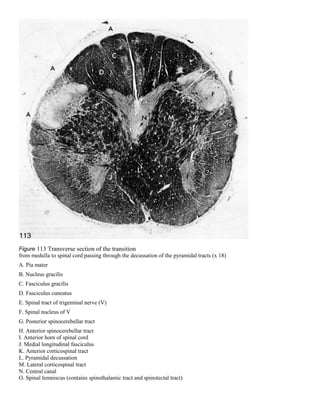

Figure 113 Transverse section of the transition

from medulla to spinal cord passing through the decussation of the pyramidal tracts (x 18)

A. Pia mater

B. Nucleus gracilis

C. Fasciculus gracilis

D. Fasciculus cuneatus

E. Spinal tract of trigeminal nerve (V)

F. Spinal nucleus of V

G. Posterior spinocerebellar tract

H. Anterior spinocerebellar tract

I. Anterior horn of spinal cord

J. Medial longitudinal fasciculus

K. Anterior corticospinal tract

L. Pyramidal decussation

M. Lateral corticospinal tract

N. Central canal

O. Spinal lemniscus (contains spinothalamic tract and spinotectal tract)

Figure 113 Transversesection of the transition from medulla to spinal cord passing through the decussation of the pyramidal tracts (x 18) A. Pia mater B. Nucleus gracilis C. Fasciculus gracilis D. Fasciculus cuneatus E. Spinal tract of trigeminal nerve (V) F. Spinal nucleus of V G. Posterior spinocerebellar tract H. Anterior spinocerebellar tract I. Anterior horn of spinal cord J. Medial longitudinal fasciculus K. Anterior corticospinal tract L. Pyramidal decussation M. Lateral corticospinal tract N. Central canal O. Spinal lemniscus (contains spinothalamic tract and spinotectal tract)